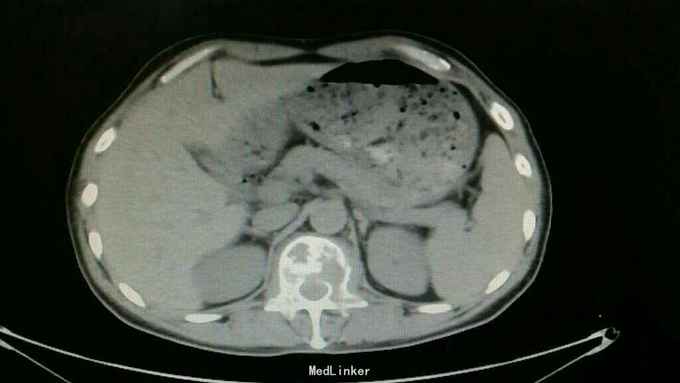

查体:脊柱生理曲度存在,无明显前凸,侧弯或后凸畸形,约胸10至腰5节段压痛及叩击痛阳性,双下肢肌张力正常,双侧股四头肌肌力约三级,双侧足背伸肌,踇背伸肌肌力约四级,双侧“4”字试验阴性,双侧直腿抬高试验阴性。肛周约15cm范围皮肤感觉减退。 辅助检查:肿瘤标志物无明显异常,血沉达120mm/h,血红蛋白111g/l,球蛋白与白蛋白比值倒置,血免疫球蛋白IgG达46.2g/l,明显升高。血清Kappa轻链与血清Lambda轻链比值明显升高。余辅助检查见下图。

通过影像学,实验室检查,骨髓穿刺检查及行CT引导下穿刺病理结果,患者多发性骨髓瘤诊断已明确。于全麻下行“腰1椎体病理性骨折病变清除减压内固定术”,术中可见病变压迫脊髓明显,彻底减压,术中出血较多,椎体破坏较重,未予骨水泥塑型,术后患者症状缓解明显,拆线后转至血液科进一步治疗。

多发性骨髓瘤是一种单克隆的浆细胞异常增生所致的恶性肿瘤,常以骨骼症状为首发,以脊柱最常累及,本例患者主要手术指征为持续且无法缓解的骨痛,并存在脊髓和神经根压迫症状,,主要影像学表现为穿凿样溶骨性改变,周围无硬化改变。很多全身骨现象无明显的阳性表现,增加了诊断的难度,上面提到的血沉升高,贫血,球白比倒置,血免疫球蛋白升高,骨髓穿刺综合判断,诊断明确后,一般行姑息性手术治疗,一般预后较差,随访见到生存期最长为4年。